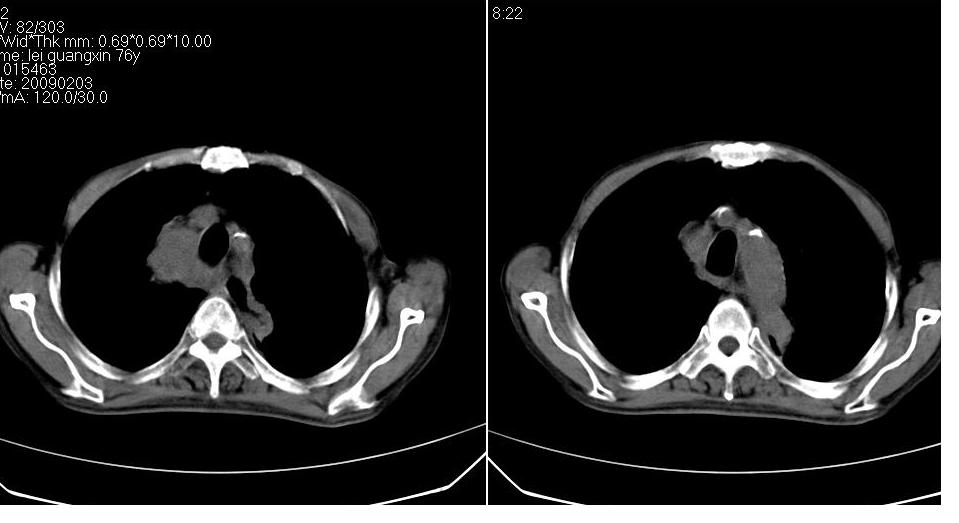

男 76岁,去年在外医院行食道癌手术,现胸闷,呼吸困难,肺窗有慢支肺气肿,无其它。

考虑----食管癌术后改变〔胃作食管重建术〕-------纵膈淋巴结转移

淋巴结转移,食道癌术后变胸腔胃。

纵隔淋巴结转移,纵隔术后改变、胸腔胃。

了解病史。支持纵隔淋巴结转移的诊断,但如果是上段食道癌术后就应考虑食道癌术后吻合口复发伴淋巴结转移。

上段食道癌术后,胸腔胃,术后吻合口复发伴淋巴结转移。